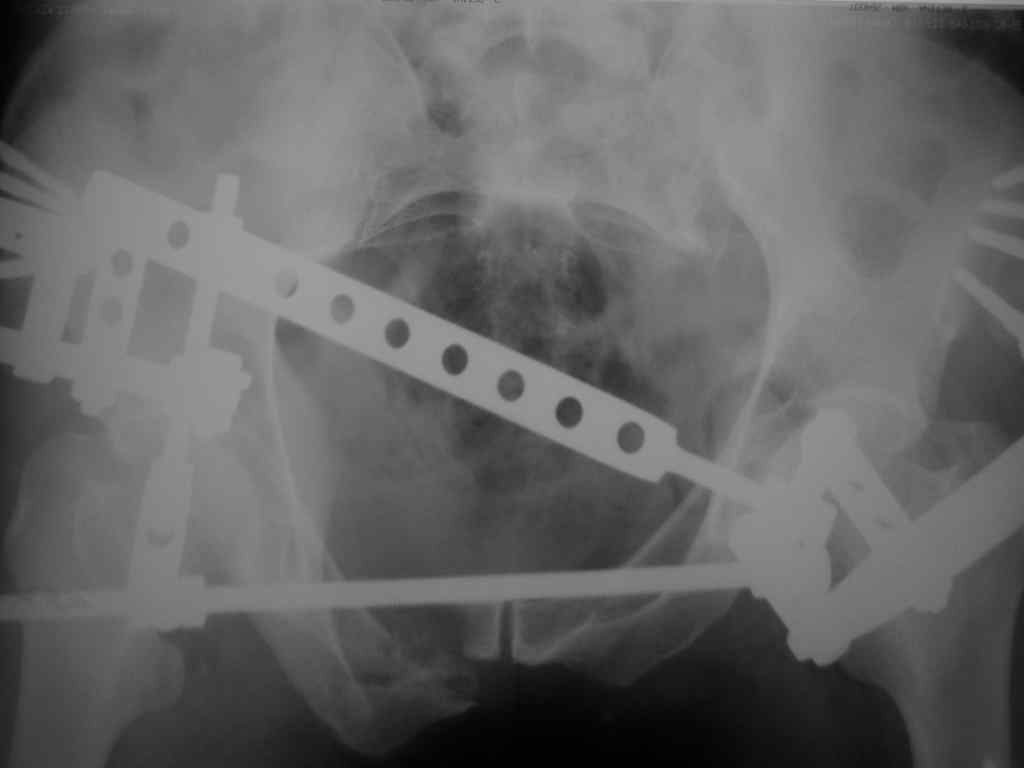

Re: Введение илиосакральных винтов

Еще снимок